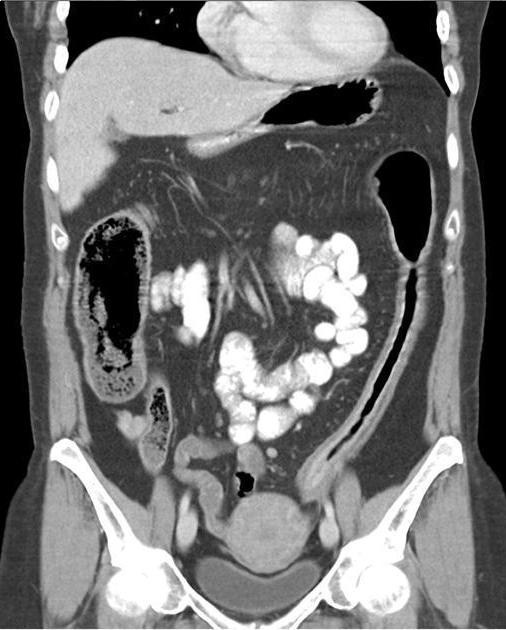

. Image TDM du maladie de

Crohn dans phase aigue est image

de epaissisement parietale avec oedeme sous muqueuse

discontinunite et signe de peigne " comb sign ". En phase

chronique cicatricielle ,aspect radiologique est image

epaissisement homogene de la paroi avec infiltration graisseuse parietale ou mesenterique

en forme de image de cible " fat halo sign". Stenose ,fistule et

abces sont des images de sa complication .

Stenose epaisissement colique

gauche et sigmoidienne avec halo graisseux d'une

maladie de Crohn . Image de hypervascularisation et

infiltration de la graisse sous-muqueuse , aspect en

peigne " Comb sign ". Image TDM en coupe coronale |